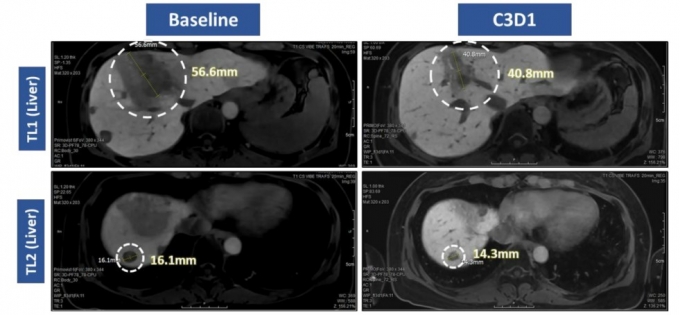

À̹ø ¹ßÇ¥¿¡ µû¸£¸é VRN10Àº Ãʱ⠿뷮ÀÓ¿¡µµ ºÒ±¸ÇÏ°í °ý¸ñÇÒ ¸¸ÇÑ Ç×Á¾¾ç È¿°ú¸¦ º¸¿´´Ù. 80~160mg±îÁöÀÇ Ãʱâ Åõ¾à±º ȯÀÚ Áß 3¸í¿¡¼ Á¾¾ç °¨¼Ò°¡ È®Àεưí, ±× Áß 1¸íÀº Á¾¾ç Å©±â°¡ 30% ÀÌ»ó ÁÙ¾îµå´Â ºÎºÐ°üÇØ(PR)¸¦ ´Þ¼ºÇß´Ù.

ƯÈ÷ HER2 Ÿ±ê Ç×ü-¾à¹°Á¢ÇÕü(ADC) '¿£ÇãÅõ'¸¦ Æ÷ÇÔÇÑ ±âÁ¸ Ä¡·áÁ¦¿¡ ºÒÀÀÇϰí Á¾¾çÀÌ ÁøÇàµÈ HER2 º¯ÀÌ À¯¹æ¾Ï ȯÀÚ¿¡¼µµ 30% ¼öÁØÀÇ Á¾¾ç °¨¼Ò¸¦ º¸¿© Æø³ÐÀº Ä¡·á °¡´É¼ºÀ» ÀÔÁõÇß´Ù.